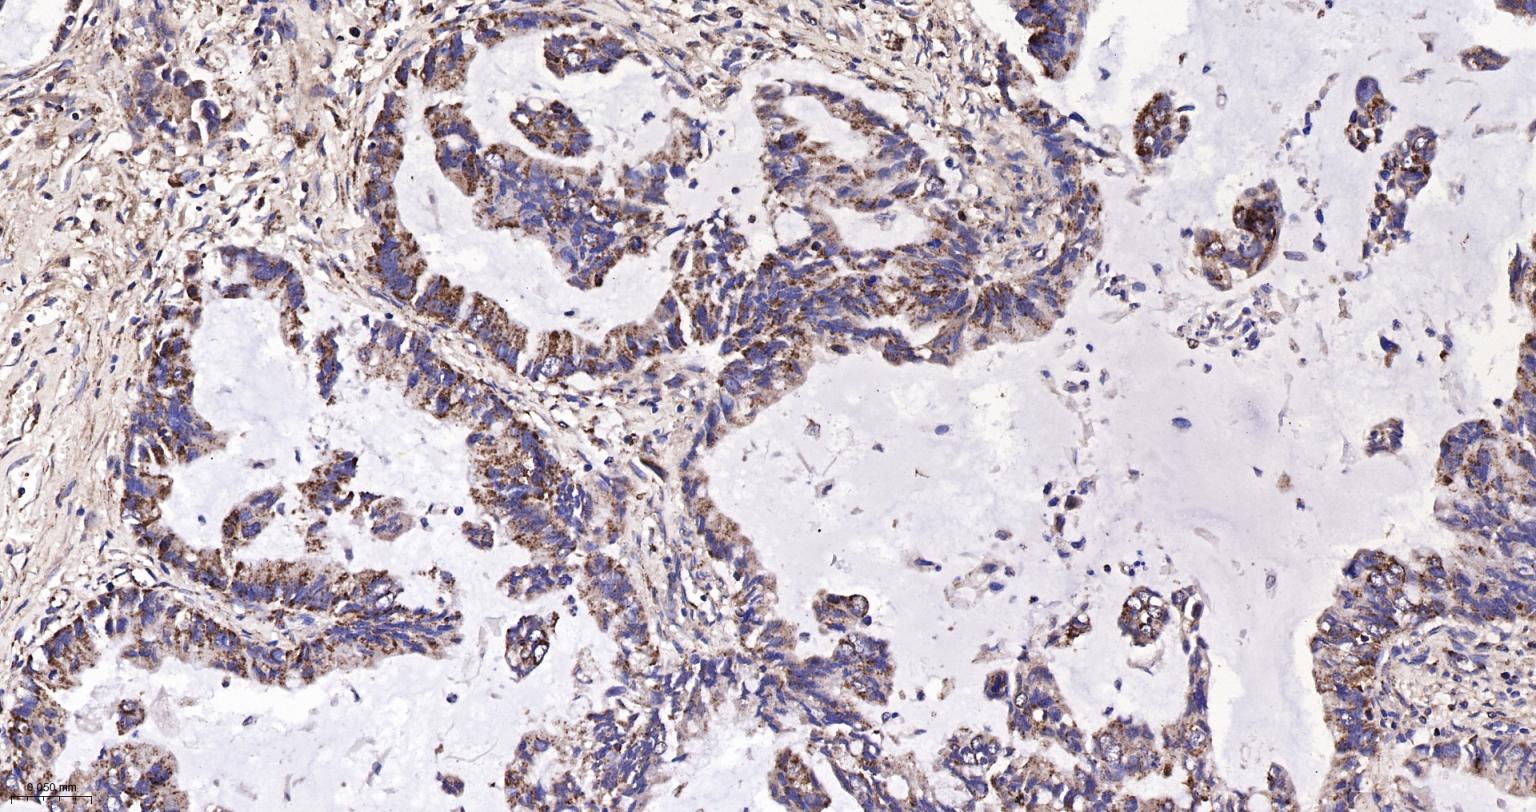

Paraformaldehyde-fixed, paraffin embedded Human Breast Cancer; Antigen retrieval by boiling in sodium citrate buffer (pH6.0) for 15 min; The section was incubated with IDH2 Monoclonal Antibody, Unconjugated (bsm-61585R) at 1:200 overnight at 4°C, followed by conjugation to the bs-0295G-HRP and DAB (C-0010) staining.